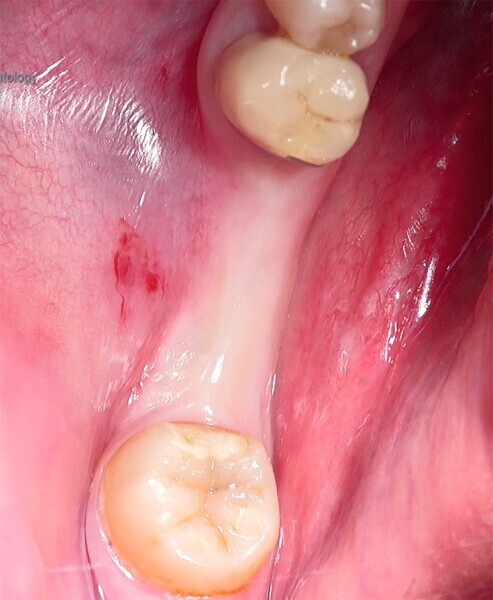

Pose immédiate d’un implant L’établissement du diagnostic clinique a révélé une fêlure dans une prémolaire, qui a contraint à l’extraction atraumatique de la dent.

Fig. 12 : Dent irrécupérable.

Fig. 13 : Dent irrécupérable.

Fig. 14 : Dent irrécupérable.

La pose immédiate d’un implant deux pièces en céramique au niveau tissulaire a été accomplie tout en préservant l’alvéole (allogreffe constituée d’un substitut osseux et protection par une membrane de collagène résorbable). La mise en charge n’a pas été réalisée à ce stade (Figs. 12–24)